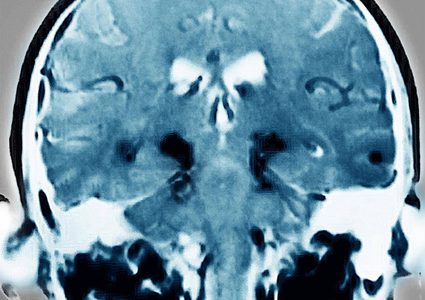

أعلن باحثون أميركيون أن مريضا بالشلل الرعاش (باركنسون) يبلغ من العمر 69 عاما، تمكن من ربط حذائه وممارسة السباحة وركوب الدراجة مجددا، بعد زرع خلايا جلدية ...

أفادت دراسة حديثة توصل عدد من العلماء إلى أهمية العمل على تحفيز بطاريات خلايا الدماغ التي تسمى «الميتوكوندريا» باستخدام النبضات الكهربائية من أجل علاج مرض الباركنسون، ...